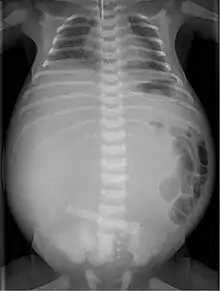

| X-ray of a newborn with meconium pseudocyst resulting from bowel perforation. In this case the cause was atresia of the terminal ileum. There is a fine rim of calcification surrounding the big pseudocyst which shifts the other intestinal structures outwards. | |